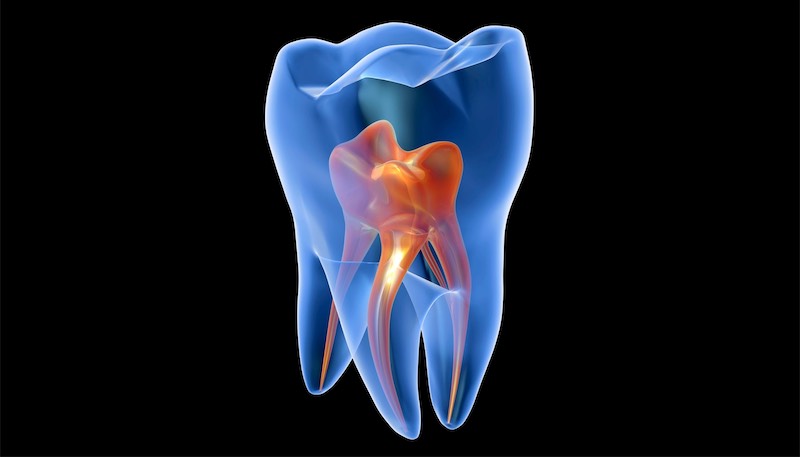

Worried about root canal pain? Modern root canal therapy in Chattanooga is virtually painless. Learn what to expect, how the process works, and why saving your tooth is always best...

Root Canal Therapy in Chattanooga: What to Expect & Does It Hurt?